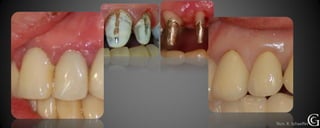

Prótesis Implanto Asistida

Las prótesis implanto asistidas, son restauraciones que utilizan los implantes

para retenerse y/o apoyarse. Los implantes sirven para reemplazar la raíz

del diente dentro del hueso, luego se realizará la restauración necesarias

(coronas, puentes, prótesis parciales o totales)

Técn. R. Schaeffer

Prótesis Implanto Asistida Lasprótesis implanto asistidas, son restauraciones que utilizan los implantes para retenerse y/o apoyarse. Los implantes sirven para reemplazar la raíz del diente dentro del hueso, luego se realizará la restauración necesarias (coronas, puentes, prótesis parciales o totales)